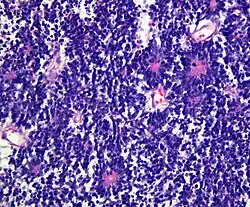

Charakteristisch sind zahlreiche sogenannte ependymoblastomatöse Rosetten. [Hämatoxylin-Eosin-Färbung]

Neuropathologisch ist für den Tumor die Ausbildung mehrreihiger Rosetten, die als ependymoblastomatöse Rosetten bezeichnet werden, charakteristisch. Angesichts der Beobachtung, dass ependymoblastomatöse Rosetten auch bei anderen embryonalen Tumoren vorkommen können, war die Bedeutung des Ependymoblastoms als eigenständige Entität bereits früh umstritten.[1]